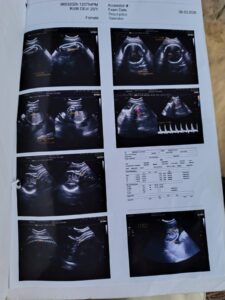

सोनभद्र तुम्हारी सात पुश्त कोढ़ी हो यह कहना है सोनभद्र जनपद के दूबेपुर गांव निवासी बिमलेश का बिमलेश ने यह पीड़ा भगवान के सामने स्वास्थ विभाग के अधिकारियों व उनकी कृपा पर पलने वाले अवैध तरीके से स्वास्थ केंद्रों का संचालन करने वालों के लिए कही बिमलेश 06 मार्च को अपनी गर्भ वती पत्नी को लेकर अल्ट्रासाउंड कराने हेतु रामगढ़ बाजार पहुंचा वहां वह किसकी सलाह पर गैलेक्सी डायग्नोस्टिक सेंटर पहुंच गया यह तो नहीं पता लेकिन वहा के रिपोर्ट के आधार पर उसका गरीबी में आटा गिला जरूर हो गया वहा पर अकुशल व्यक्ति द्वारा अल्ट्रासाउंड किए जाने का परिणाम ये रहा कि उसे अपना खेत गिरवी रखना पड़ गया 06 मार्च को उक्त केंद्र द्वारा जो रिपोर्ट दी गई है वह पूरी तरह भ्रामक और स्वास्थ्य महकमे पर सवाल खड़ा करने वाली है रिपोर्ट में दर्शाया गया है कि उसके गर्भ में एक बच्चा है जब कि आप्रेशन के दौरान दो बच्चे पैदा हुए आपरेशन के बाद एक बच्चे की मौत हो गई जिस निजी अस्पताल में बिमलेश की पत्नी रूबी का आपरेशन हुआ वह अस्पताल भी किसी से कम नही विमलेश के अनुसार 70 हजार रुपए उक्त अस्पताल ने लिया उसके अलावा जो शिशु जीवित बच गया था उसके उपचार में भी वह अब तक 70 से 80 हजार रुपए खर्च करने की बात बता रहा है इस संबंध जब जानकारी का प्रयास किया गया तो ९१२९००७५६५ नंबर से फोन आया और बताया गया के मै गैलेक्सी डायग्नोस्टिक सेंटर से बोल रहा हूं हमने रिपोर्ट में लिखा था रिस्केन इसका मतलब होता है पुनः जांच करवाए रिपोर्ट में लिखा है लेबल टू । जबकि लेबल टू उस समय होता है जब भ्रूण पांच से सात सप्ताह का होता । जानकारों का कहना है कि सारी रिपोर्ट कमियों के दायरे में है।

क्षेत्र के लोगों का कहना है कि इस सेंटर पर कोई रेडियो लॉजिस्ट नहीं फिर भी धड़ल्ले से कारोबार चल रहा है। इसमें स्वास्थ्य विभाग के कतिपय अधिकारियों की भूमिका भी संदिग्ध है।